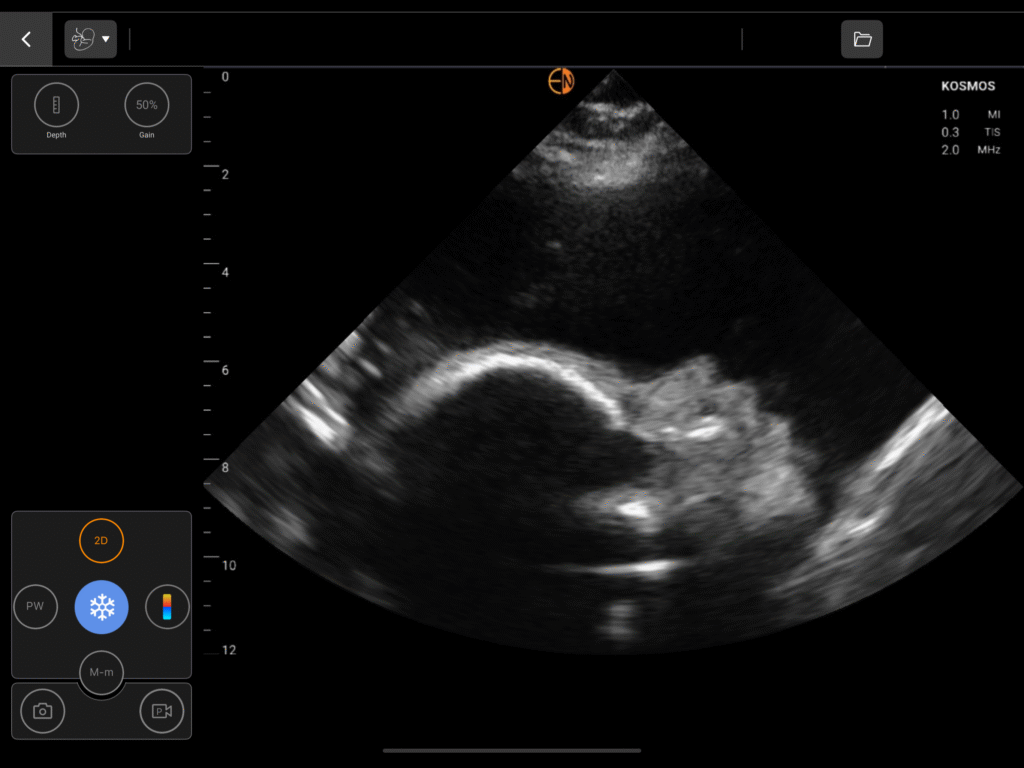

Comprehensive OB Biometry

A complete measurement and calculation package for all three trimesters, including Gestational Sac (GS), Crown Rump Length (CRL), Biparietal Diameter (BPD), Head Circumference (HC), Abdominal Circumference (AC), and Femur Length (FL).

Assess fetal head position, station, and presentation (cephalic/breech) to guide labor management.

OB/GYN Image Gallery